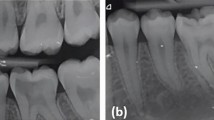

The evaluation of pulpotomy efficacy in mature permanent teeth is divided into clinical and radiographic criteria involving examination of the symptoms and signs of the affected tooth, pulp electrical test, temperature test, and X-ray image at 6, 12, and 24 months and, if needed, once a year for the next four years (Table 4).18,92,93,94 LDF or PO may also be employed to monitor the blood supply of the dental pulp for a long time. Besides, from a histological perspective, successful pulp preservation therapy is characterized by developing a restorative dentin bridge. Previous studies have shown a correlation between the formation of dentin bridges with a higher success rate.56,95,96